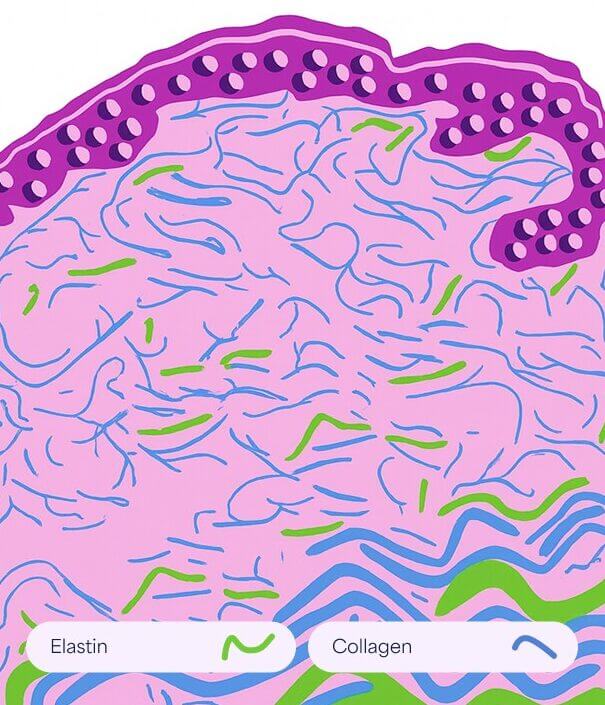

Feine Linien und

Falten

Dieser Alterungsprozess geht mit strukturellen und funktionellen Veränderungen von extrazellulären Matrixkomponenten wie Kollagen und Elastin einher. Dies führt zur Entstehung von feinen Linien und Falten.

Zhang, S., & Duan, E. (2018). Kampf gegen die Hautalterung: Der Weg von der Grundlagenforschung zur klinischen Anwendung. Zelltransplantation, 27(5), 729–738.

So funktioniert es

- Fördert den Abbau von altem, geschädigtem Kollagen

- Es induziert die Proliferation von Keratinozyten, die Wachstumsfaktoren freisetzen, um die Kollagenablagerung durch Fibroblasten und die Elastinablagerung zu fördern.

- Moduliert die Expression mehrerer Gene in der Haut (vaskulärer endothelialer Wachstumsfaktor, Fibroblasten-Wachstumsfaktor, epidermaler Wachstumsfaktor, Kollagen Typ I und III), die die Umgestaltung der extrazellulären Matrix fördern.